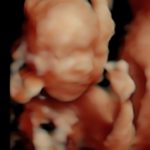

4D/5D/HD Ultrasound Gallery

Gallery